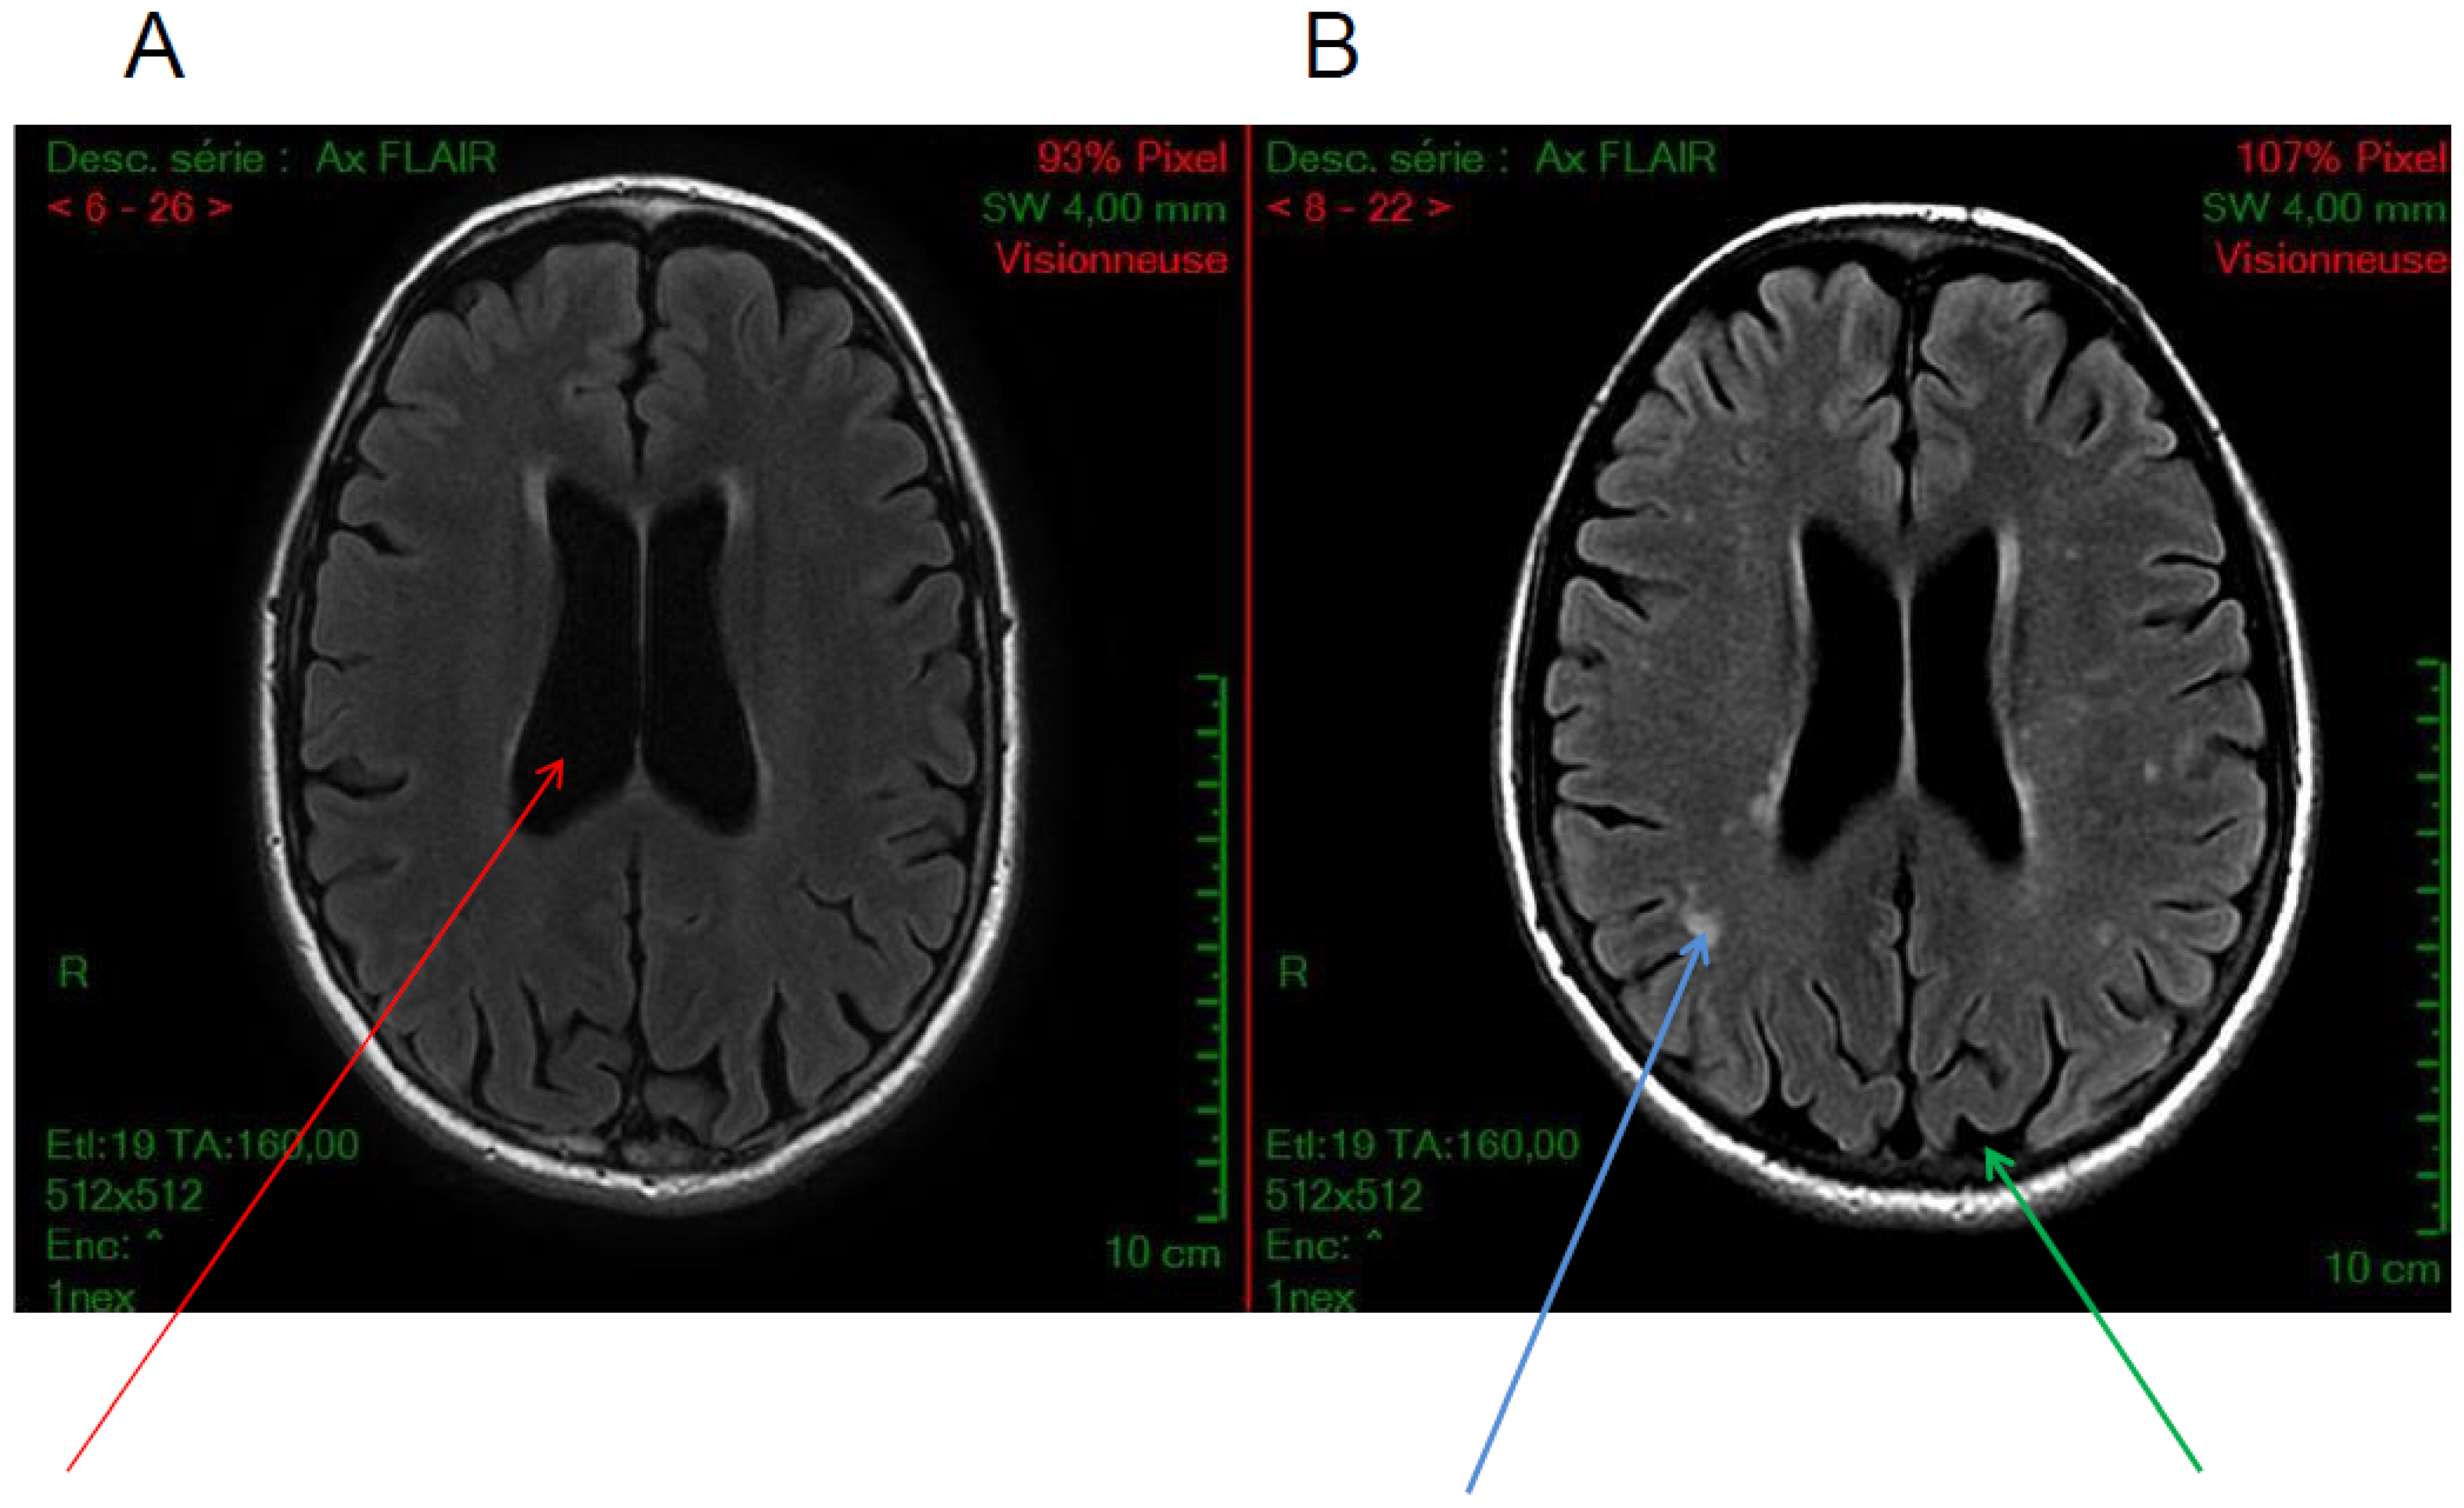

5.3. White Matter Hyperintensities

5.4. Others